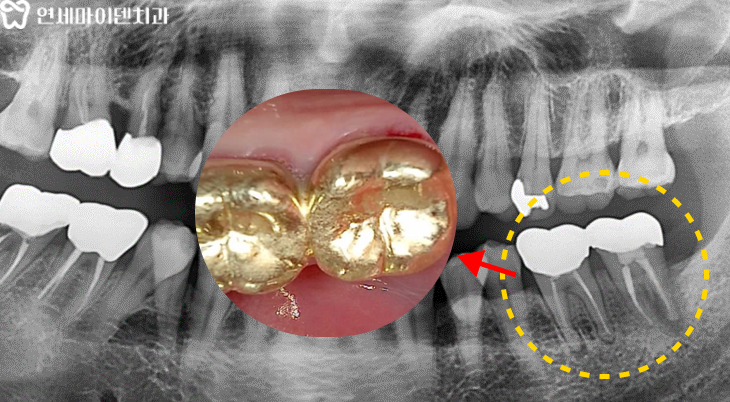

이 환자분은 아래쪽 어금니 2개에 문제가 있었습니다.

염증이 크고 다른 치과에서 발치 권유를 받았지만

최대한 치아를 살리고 싶으셔서 저희 병원을 찾아오셨습니다.엑스레이 상에서 넓은 부위의 염증을 확인했지만

신경치료를 하기 전 어금니에 씌워져 있던 크라운을 제거하고

미세현미경으로 내부를 확인하였습니다.이 과정에서 엑스레이로 확인되지 않았던

치아의 금, 즉 크랙라인이 확인되었습니다.금이 간 치아는 살릴 수 없나요?

이 환자분도 미세현미경 상으로 명백한 크랙라인이 확인됐기 때문에

지체없이 발치한 후 임플란트를 진행하기로 했습니다.당일 수술이 결정되었지만, 3D 네비게이션 정밀 진단을 통해